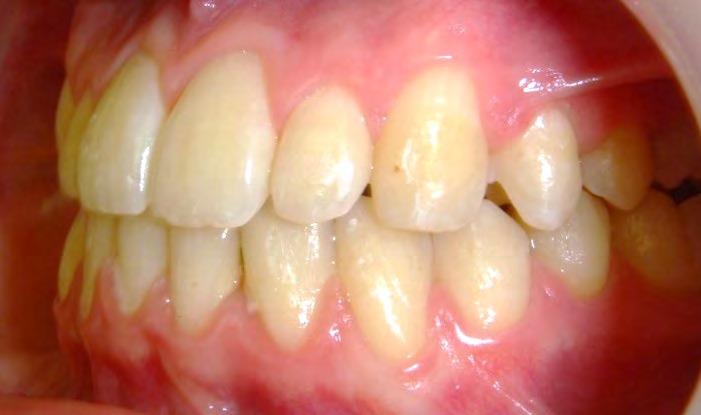

Below are cases treated at Vakresmil without extractions within the last three years. The families had been told, “It is simply not possible for your child to be treated without extractions” by orthodontists. Judge for yourself if that was right or wrong.

The overall aim is to produce the best smile we can — a “beautiful smile”, if you will — without premolar extractions, headgear, facemasks or banded appliances. A smile that both the patient and we at Vakresmil can be proud of.